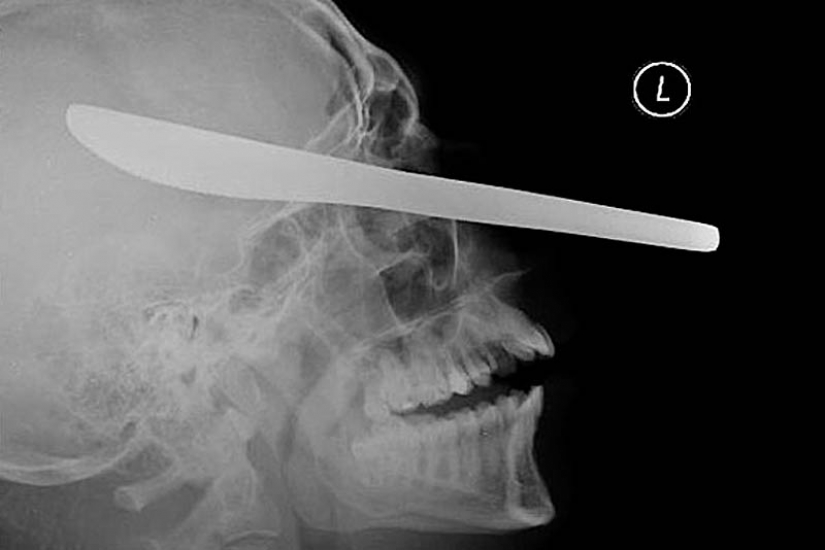

19. Knife for cutting oil in the eye of the patient.